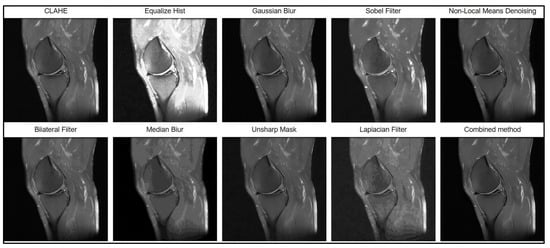

The filter preprocessing stages, which are shown in Figure 3, involved the investigation and testing of contrast enhancement (CLAHE, Equalize Hist), noise reduction (Gaussian Blur, Median Blur, Bilateral Filter, Non-Local Means Denoising), and sharpening (Unsharp Mask, Laplacian Filter, Sobel Filter) techniques. The metrics of MSE (mean square error), pSNR (peak signal-to-noise ratio), and SSIM (structural similarity) were used for performance evaluation.

Figure 3.

Stages of filter preprocessing of images.

For a visual assessment of the effectiveness of each filter, Figure 4 presents the image preprocessing results obtained using the tested algorithms. The displayed MRI image fragments allow a visual comparison of the degree of noise suppression and the preservation of anatomical details for each method.

Figure 4.

Results of image processing using various methods.

Based on the results of the comparative analysis, the combined approach of Non-Local Means Denoising and Unsharp Mask was selected, as it demonstrated the best quantitative performance (MSE = 32.55; PSNR = 41.37; SSIM = 0.92), indicating its high effectiveness in MRI image preprocessing. In addition, this method produced the most visually satisfactory results, achieving optimal noise suppression while preserving anatomical boundaries (Figure 5).